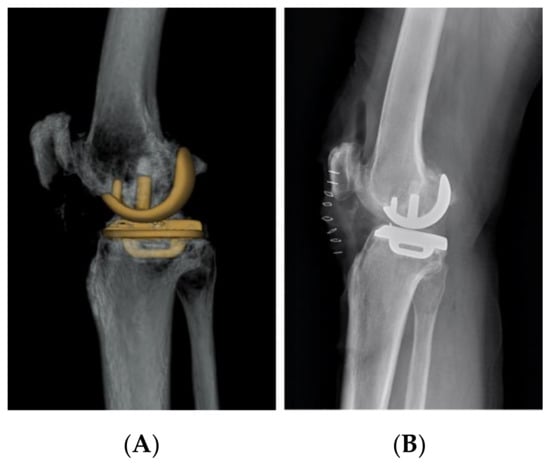

2. Materials and Methods